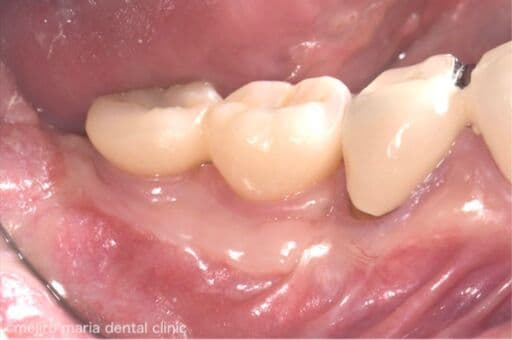

歯肉移植の症例

インプラントを守るために強い歯茎を移植(FGG)

インプラントの周りの硬い歯茎が失われた患者様に対する、歯茎再生の手術(付着歯肉を増やすための歯茎の移植)を行った症例です。

before

after

治療内容 遊離歯肉移植術(FGG)

治療期間 3ヶ月(移植した歯茎が落ち着くまで)

治療回数 1回(他、抜糸や経過観察を除く)

治療費用 137,500円(税込)

症例から言えること

抜歯すると、骨のボリュームと歯茎のボリュームが下がるため、強い歯ぐきも同時に失われます。その結果、インプラントを埋入するときに必要な付着歯肉が得られない(3mm以下)状態になってしまうケースは少なくありません。この症例の患者様のように硬い歯茎が失われていると、インプラントが長持ちしないことが多くの研究で明らかになっています。インプラントは虫歯になることはありませんが、歯周病になることはあります。インプラントをできるだけ長く使用するために、インプラント周囲炎に罹患させないよう、清掃性を高め、インプラント周囲を清潔に保つことは非常に重要です。